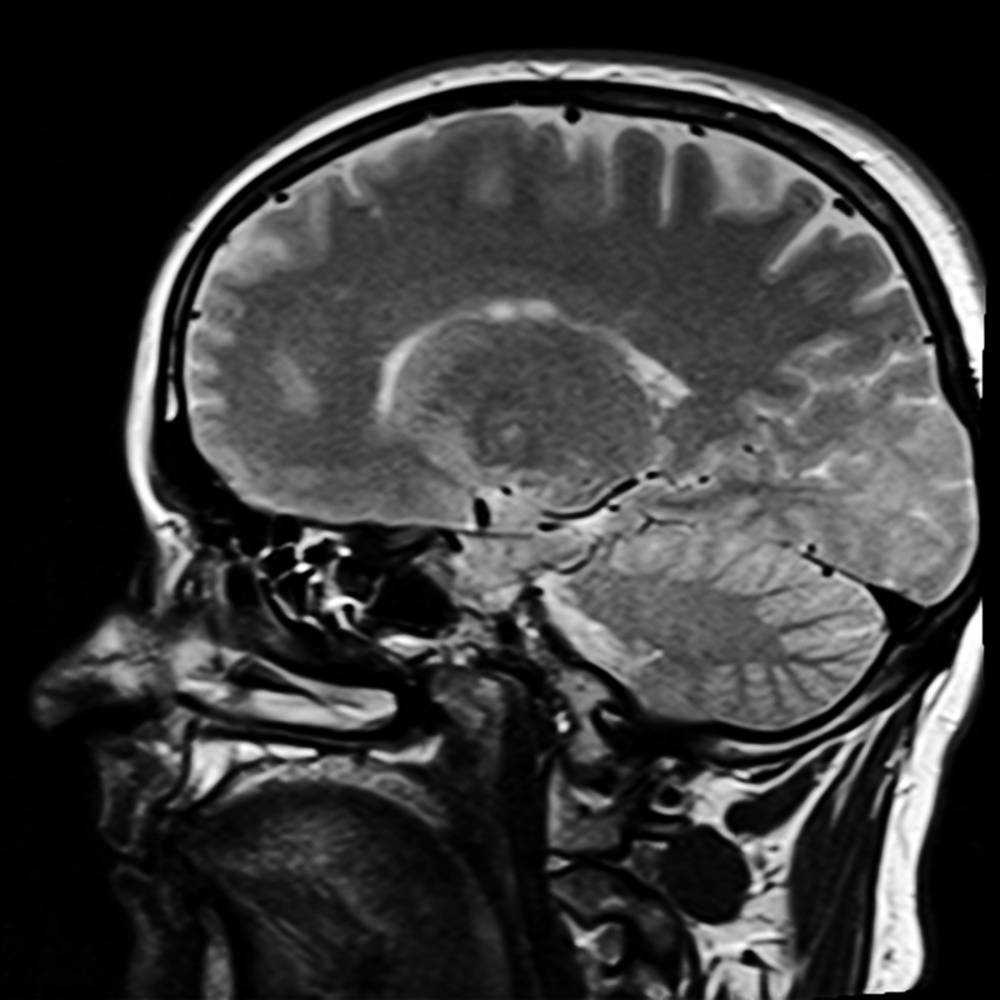

Анализ состояния сосудов головного мозга необходим для визуализации признаков атеросклероза, инсульта, аневризмы. Показаниями к магнитно-резонансной томографии служат: ухудшение зрения или слуха, травмы, постоянные головные боли, ослабление внимания, памяти. Метод помогает выявить:

Работу мозга может ухудшать ангиома, если сосуды, расширяясь переплетаются между собой. Аппарат укажет форму, расположение, размеры, степень сдавливания. При атеросклерозе нарушается кровообращение, МРТ показывает плотность и величину скоплений бляшек.

Высокая точность томографа определяет нарушения в крупных и мелких сосудах. На изображении можно оценить состояние капилляров, закупоривание бляшками, тромбами. Инсульт — острая форма нарушения мозгового кровообращения. Диагностика выявляет поврежденный участок, демонстрирует степень осложнений.